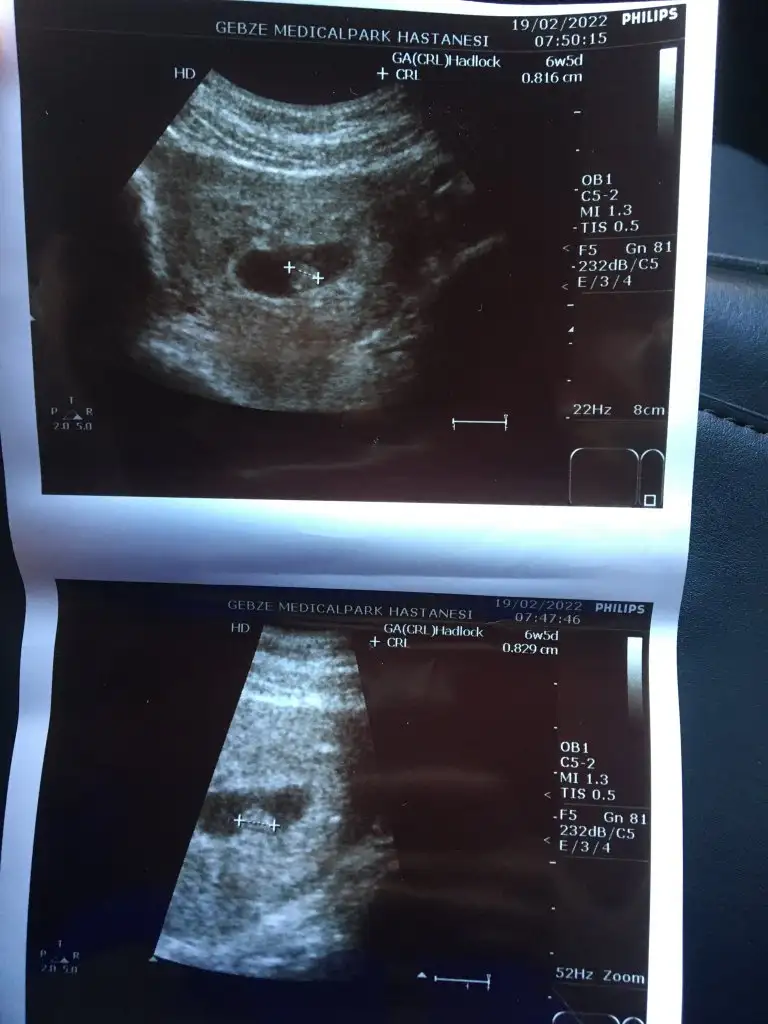

Bugün 7+0 , bebek ise 6+5 çıktı. Kalp atışı başta olması gerekene göre yavaştı. 0,81 mm yaklaşık bebitomkalp atışını da videoya aldık bu sefer